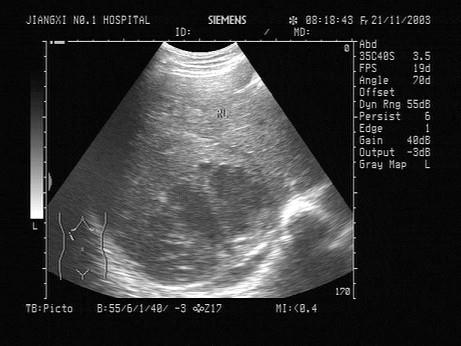

一患者,发热,右上腹痛,血常规检查白细胞增多。结合超声声像图,诊断为?(?)A.肝脓肿B.肝血管瘤C.肝癌D.脂肪肝E.肝囊肿

问题 一患者,发热,右上腹痛,血常规检查白细胞增多。结合超声声像图,诊断为?(?)

选项 A.肝脓肿 B.肝血管瘤 C.肝癌 D.脂肪肝 E.肝囊肿

答案 A